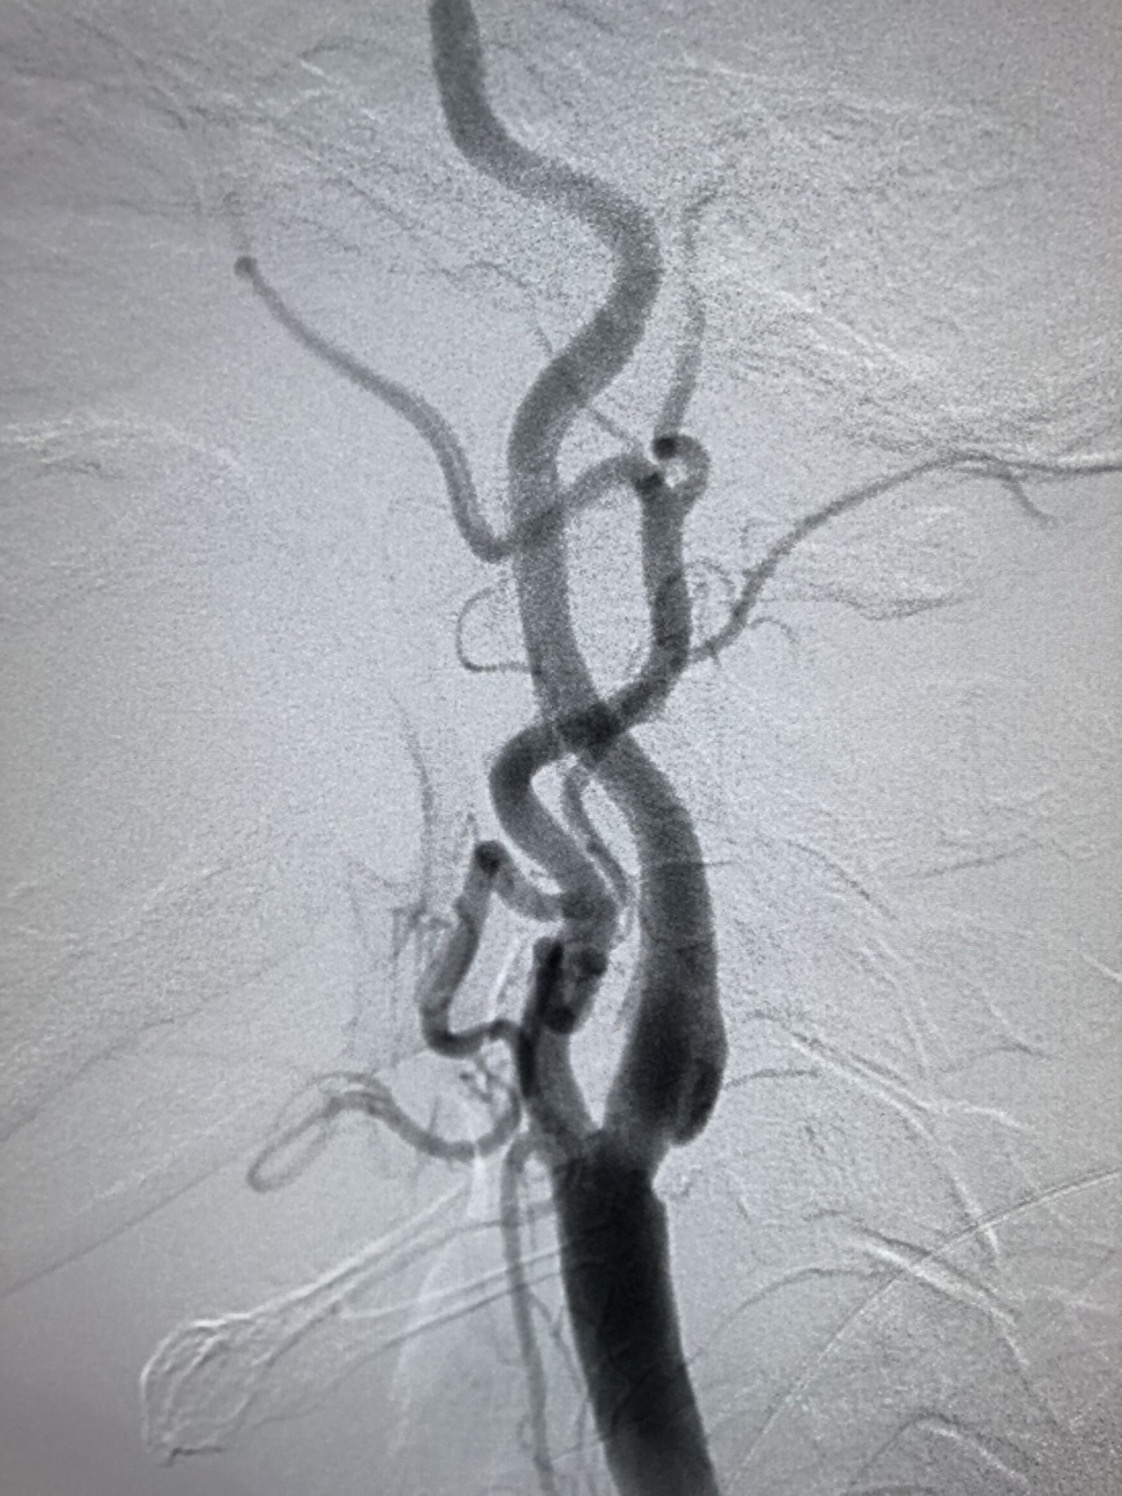

DSA:左侧颈内动脉起始部轻度狭窄。

DSA:左侧颈内动脉代偿右侧半球血供。

明确诊断后,考虑患者存在缺血症状,造影提示颈内动脉线性狭窄,同时右侧颈内动脉窦部可见粥样硬化斑块伴溃疡,系患者的罪犯血管。同时因患者后循环血管发育不良,基底动脉纤细伴狭窄,后循环血供均由前循环胚胎型大脑后动脉供应。不积极干预,出现恶性卒中风险极大,因患者颈部较短,且病变部位偏高,建议患者行颈动脉支架成形术。